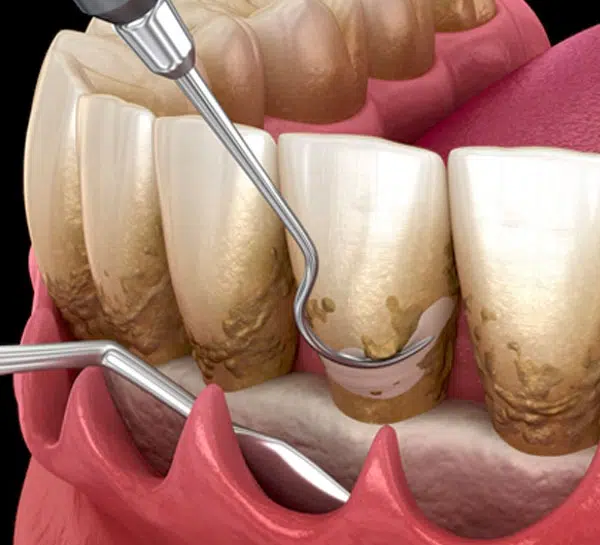

Often called a "deep cleaning," this two-part procedure treats gum disease. Scaling removes hardened plaque (tartar) both above and below the gum line, and Root Planing smooths the tooth roots, making it harder for bacteria to reattach.

It is essential for stopping the progression of gum disease (periodontitis). This treatment prevents bone loss around the teeth, eliminates chronic bad breath, stops gum recession, and ultimately saves your teeth from needing extraction.

For the first 24-48 hours, avoid very hot and very cold foods to minimize sensitivity in the treated areas. Also, avoid extremely chewy or very hard foods that require excessive chewing on the day of the procedure.